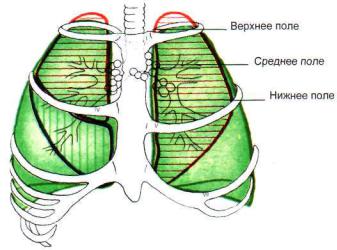

Анатомические изображения сегментов легких различных животных

Раздел: Другие животные